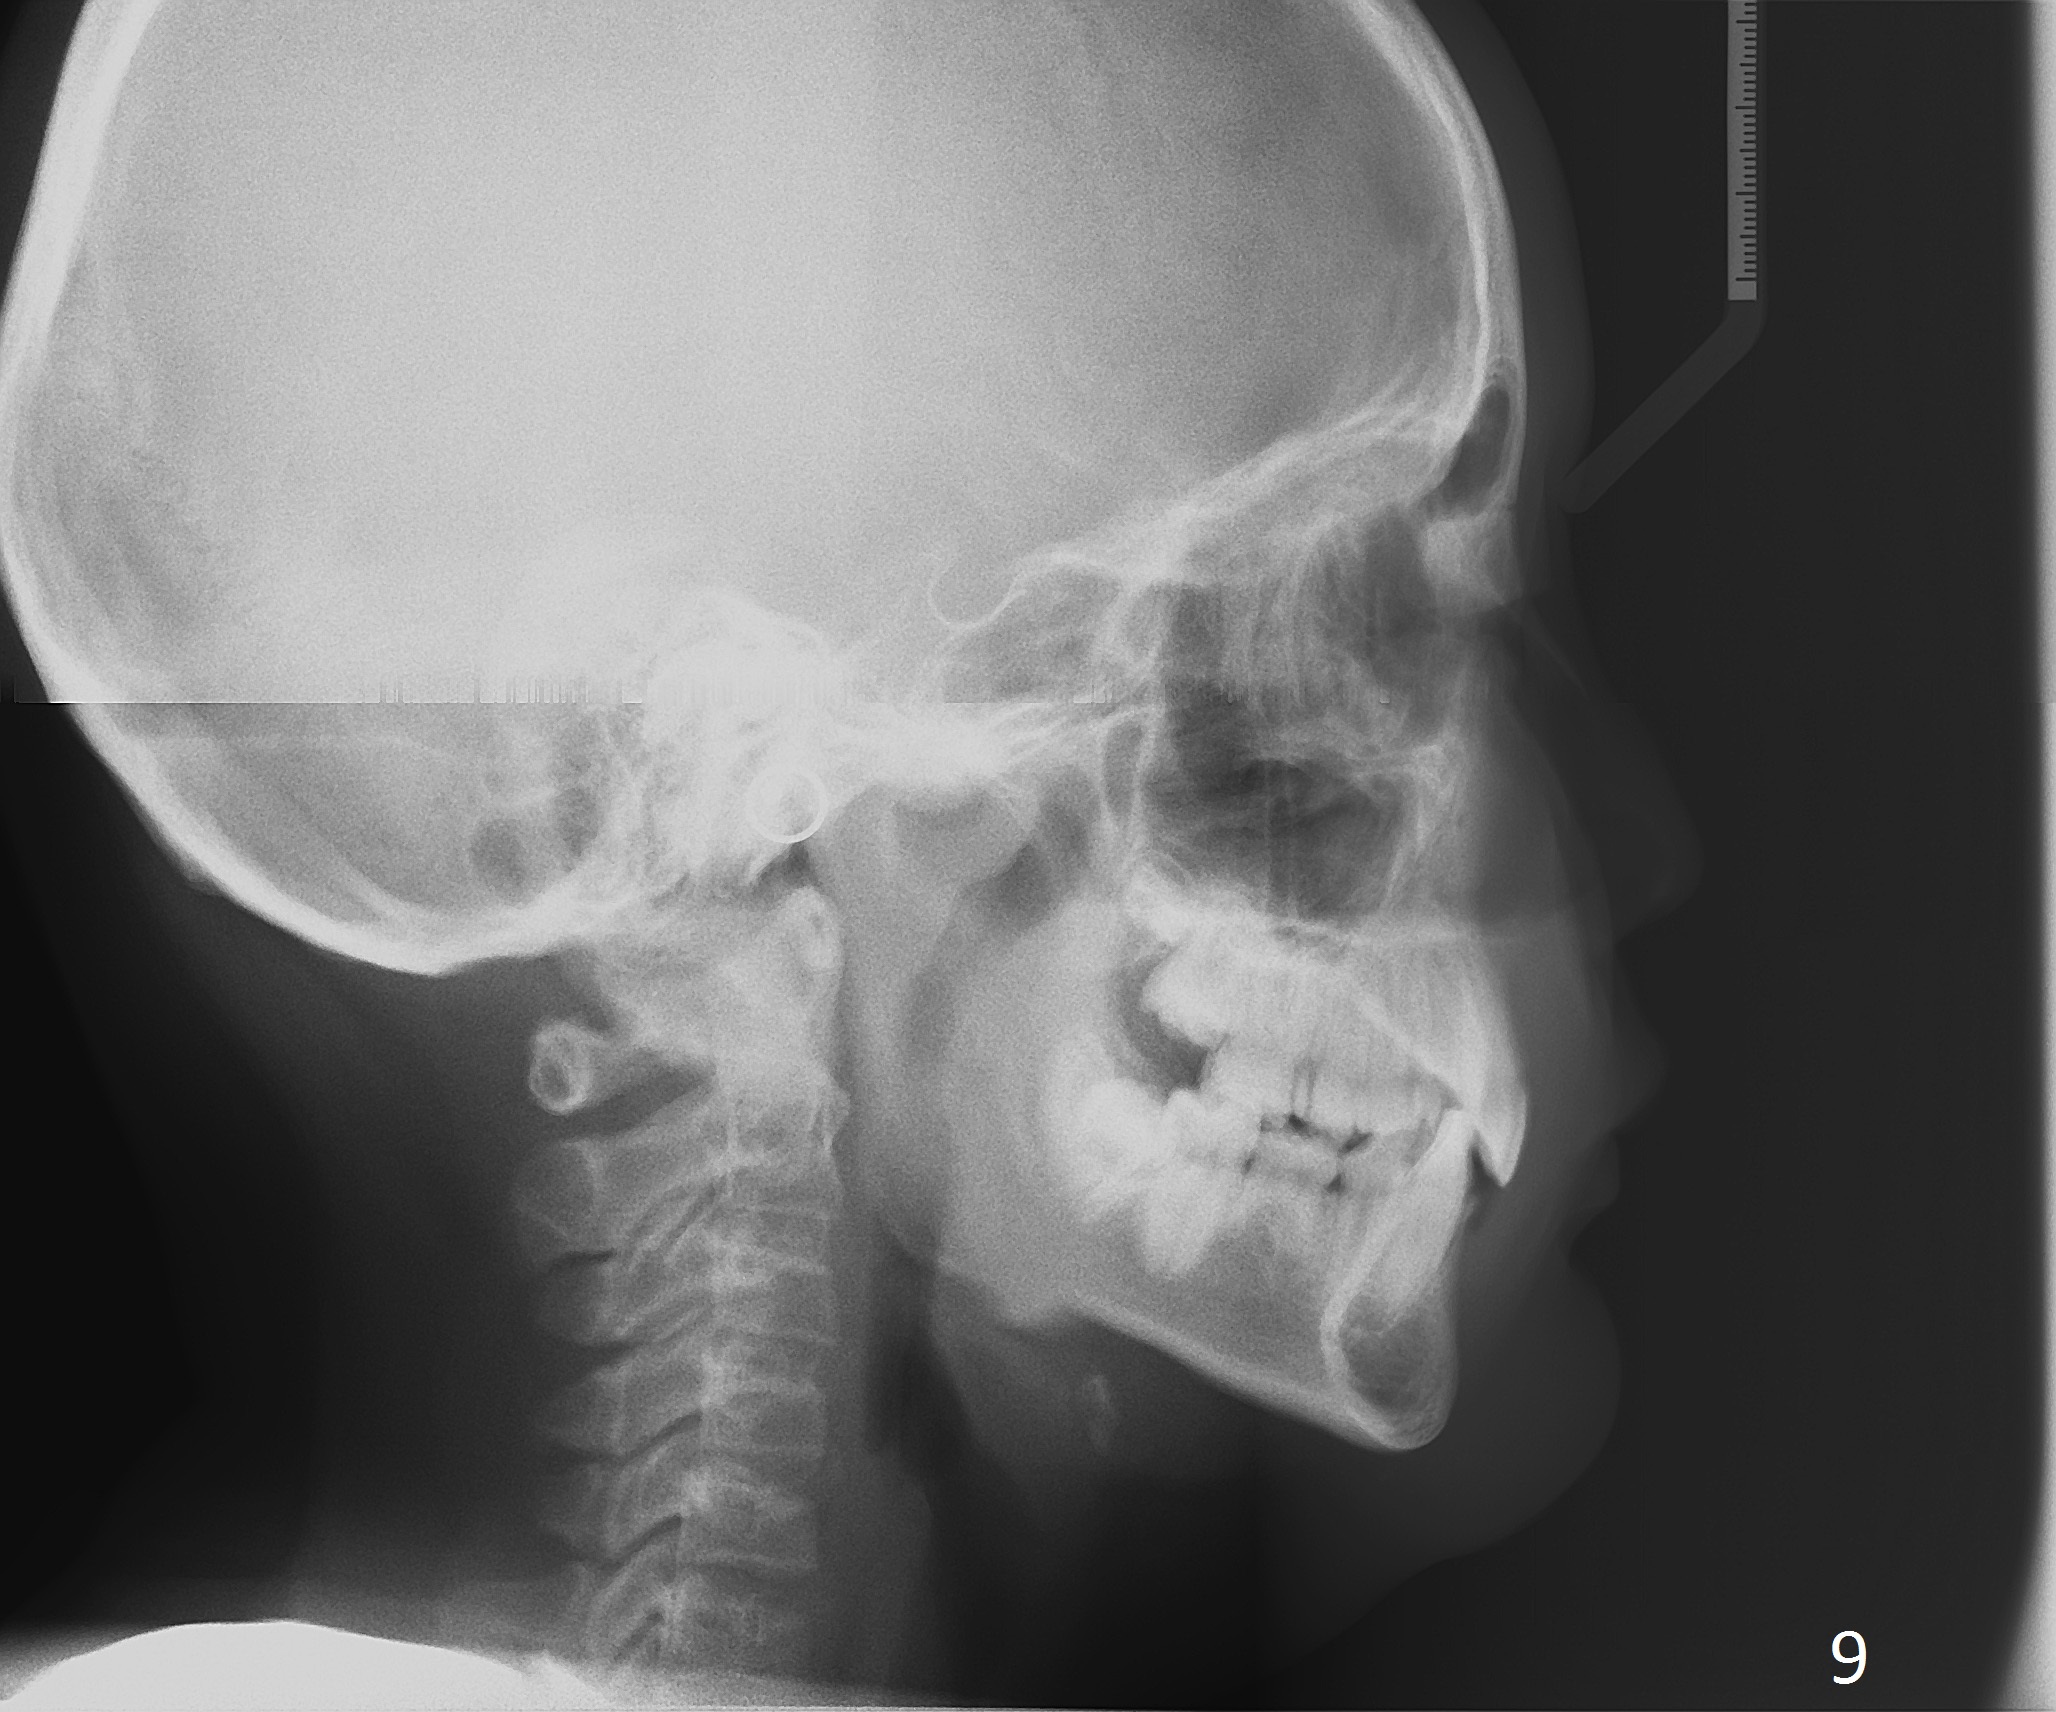

A 11-year-old boy has shorter lower 1/3 face (Fig.1,2) with light concave profile, especially the lower lip (Fig.3).  There is anterior deep bite (Fig.4) with Class II posterior occlusion (Fig.5,6).  UL2 is microdontia (Fig.7 *), while the Lower Es are retained (Fig.8).  Preop (2015_01_07) Ceph (Fig.9) and Pan (Fig.10) show ectopic L7s and congenitally missing L5s.